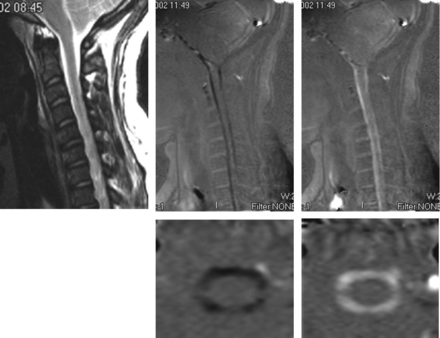

PCMR images in sagittal (upper row) and axial (lower row) views showing flow in one systolic and one diastolic phase of the cycle and for reference (top left) the sagittal T2-weighted image in the patient. These demonstrate more flow anterior to the cord than posterior. On careful inspection, the axial images show more flow anterolateral to the cord than posterior to it. Reproduced with permission from Hofkes SK, Iskandar BJ, Turski PA, et al. Differentiation between symptomatic Chiari I malformation and asymptomatic tonsilar ectopia by using cerebrospinal fluid flow imaging: initial estimate of imaging accuracy. Radiology 2007;245:532–40.